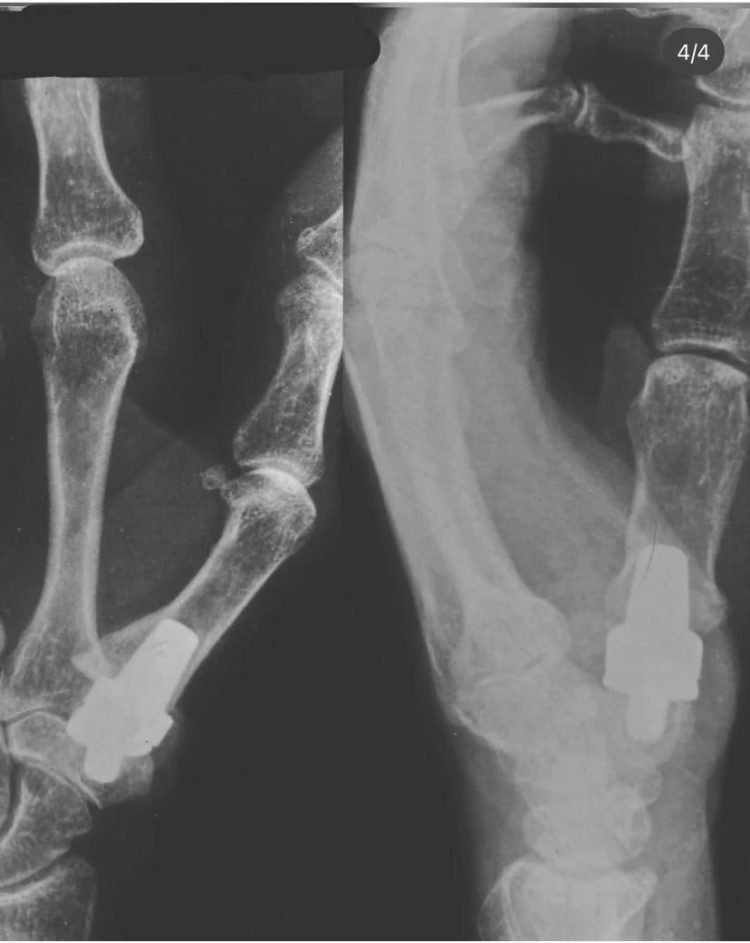

Пфс 1 пальца

Пфс 1 пальца 143 фото